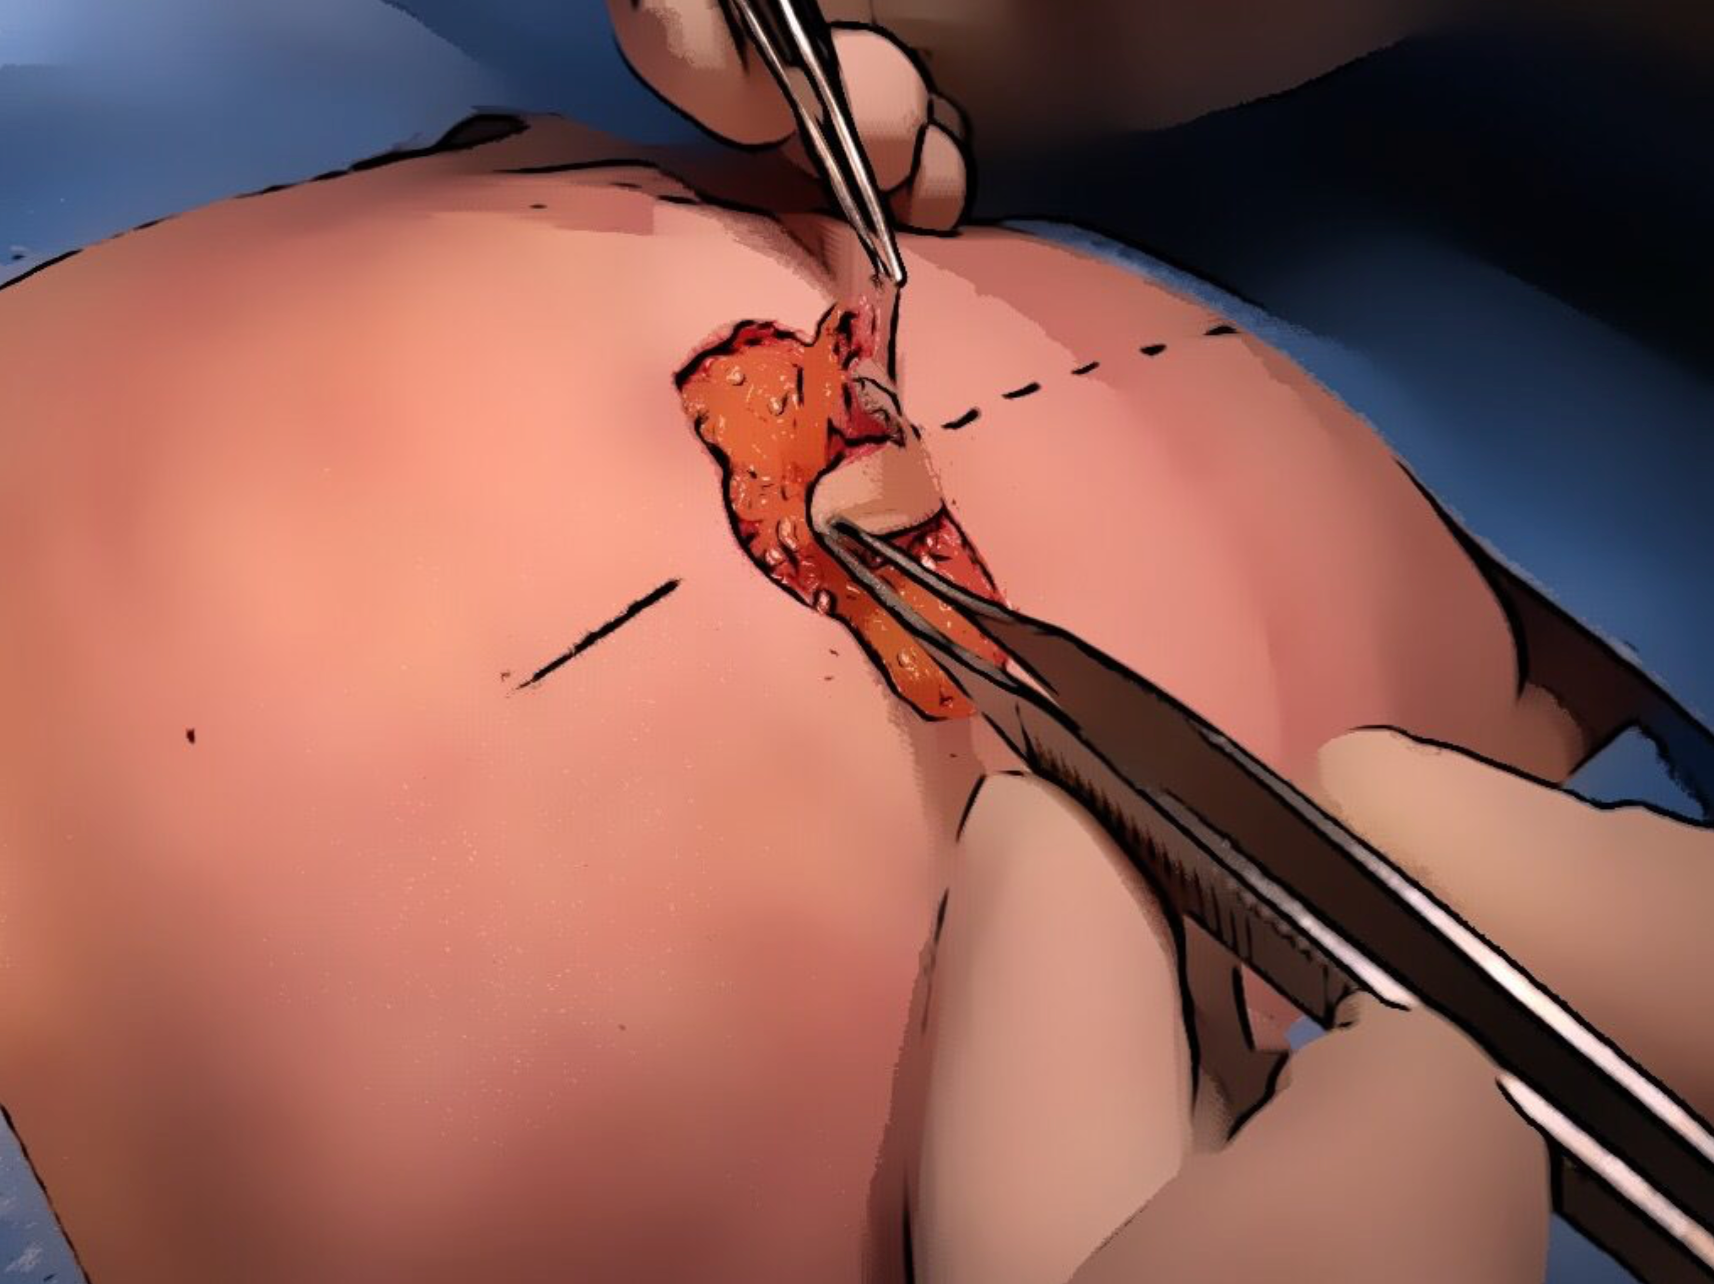

Isoleren bloedvat

Het bloedvaatje of perforant wordt voorzichtig geïsoleerd en vrij gelegd. De spieren worden niet meegenomen en blijven intact.